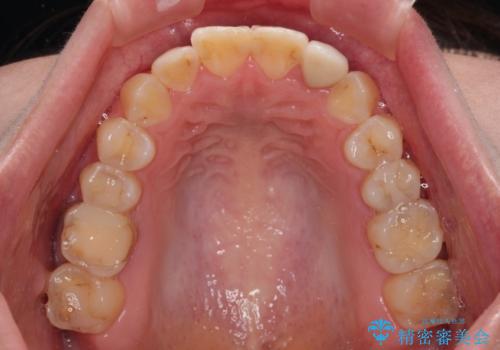

開咬を治す インビザラインによる矯正治療

- 上下前歯の開咬を気にして来院された患者様です。

開咬はインビザラインを用いると有意に改善ができるため、インビザラインによる矯正治療を行うこととしました。

途中1年8ヶ月ほど来院されず、久しぶりの来院後は治療が面倒とのことで、前歯の叢生や隙間に不十分な点が残った状態での終了となりました。